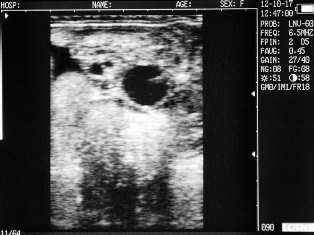

Ultrasound images of cows reproductive system, generated by a scanner Sonovet with rectal linear transducer.

Cow with calf. Deadline - 25 days